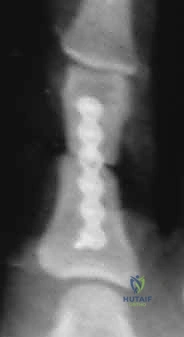

- المتابعة الدورية: يتطلب العلاج التحفظي إجراء أشعة سينية أسبوعية خلال الأسابيع الثلاثة الأولى للتأكد من عدم انزياح الكسر من مكانه.